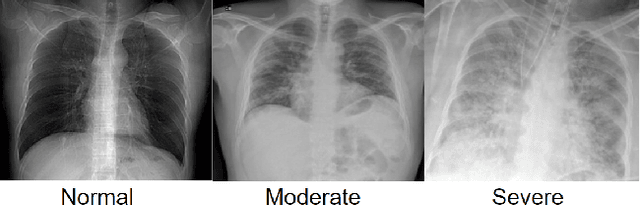

Abstract:The COVID-19 pandemic strained healthcare resources and prompted discussion about how machine learning can alleviate physician burdens and contribute to diagnosis. Chest x-rays (CXRs) are used for diagnosis of COVID-19, but few studies predict the severity of a patient's condition from CXRs. In this study, we produce a large COVID severity dataset by merging three sources and investigate the efficacy of transfer learning using ImageNet- and CXR-pretrained models and vision transformers (ViTs) in both severity regression and classification tasks. A pretrained DenseNet161 model performed the best on the three class severity prediction problem, reaching 80% accuracy overall and 77.3%, 83.9%, and 70% on mild, moderate and severe cases, respectively. The ViT had the best regression results, with a mean absolute error of 0.5676 compared to radiologist-predicted severity scores. The project's source code is publicly available.